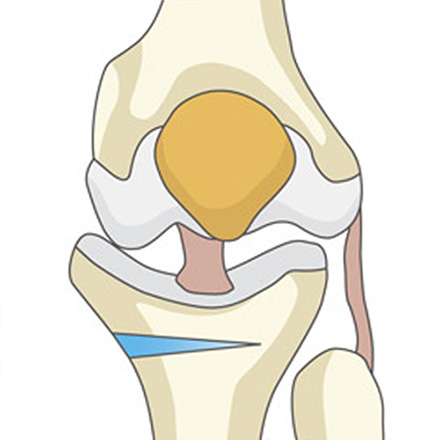

최소절개 무릎 절골술 과정

-

01

정강이뼈(경골) 윗부분을 약 3~5cm 절개한 뒤, 정강이뼈에 금을 냅니다.

02

정강이뼈 윗부분을 미세하게 벌려 인공뼈를 넣을 공간을 만들어줍니다.

03

벌려진 공간에 인공뼈를 넣어 틀어져 있던 다리 축을 정상 각도로 바로잡습니다.

04

바로잡은 각도가 잘 유지되도록 금속 플레이트와 나사로 단단히 고정합니다.